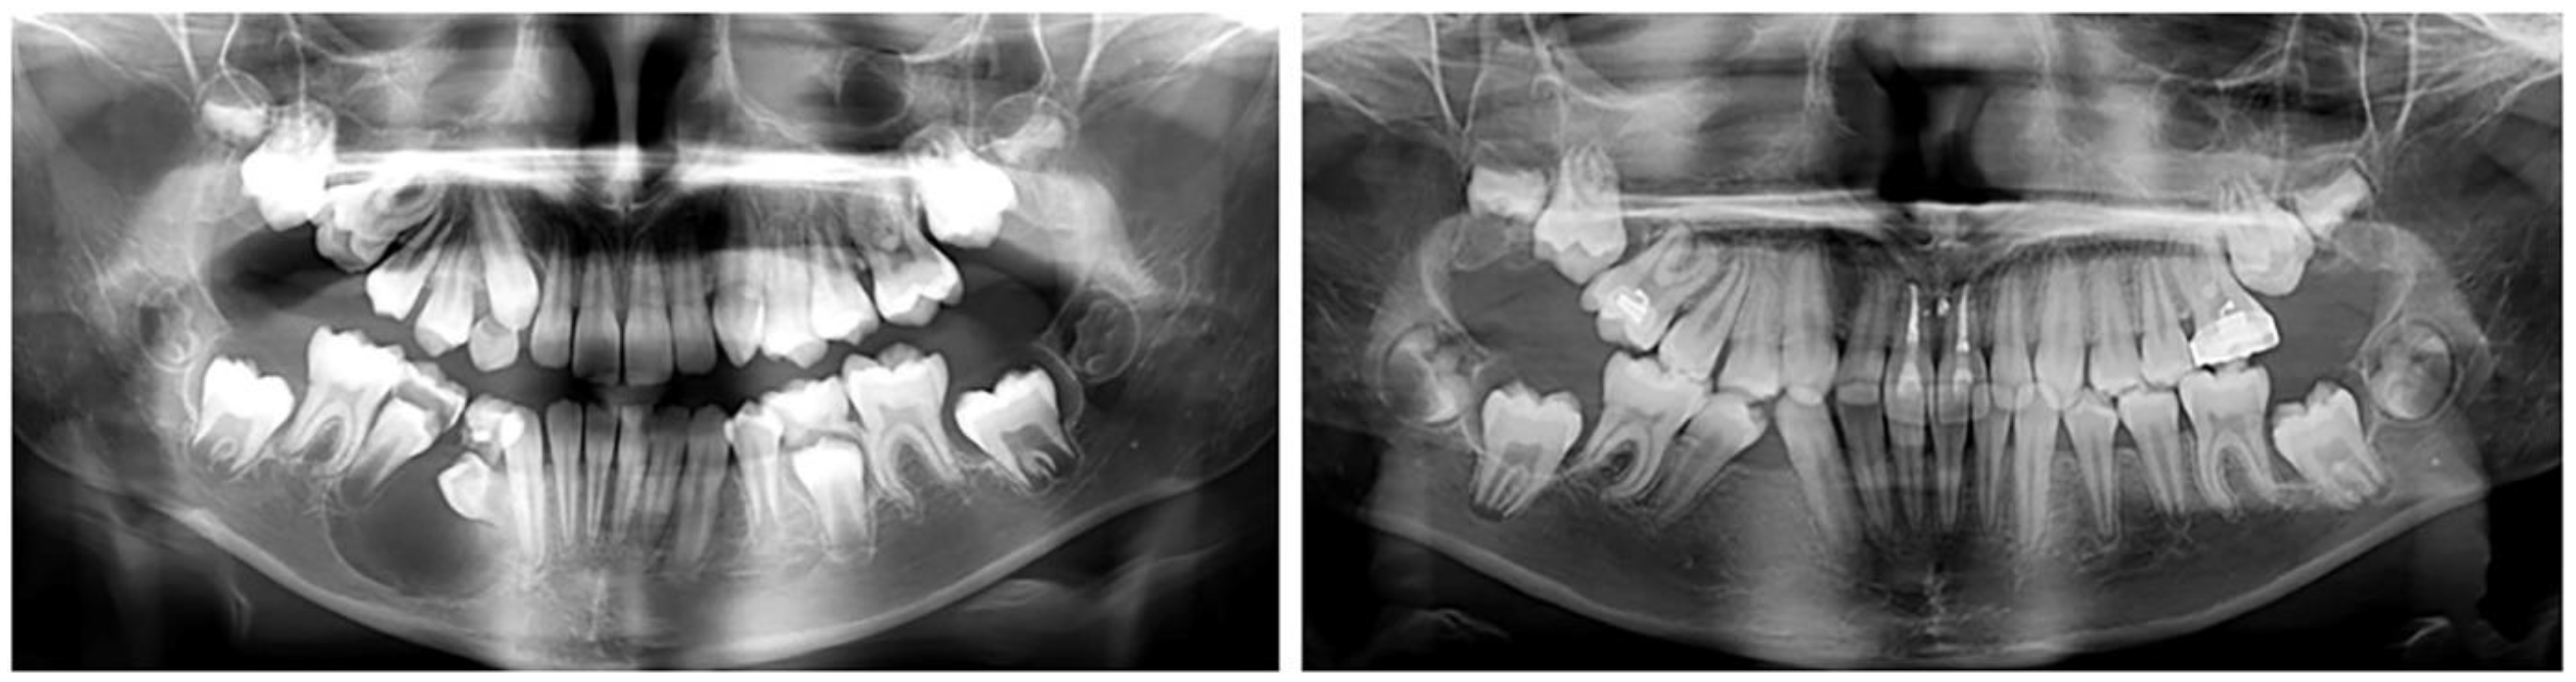

2.2.2. Clinical Case 2–Impaction of Upper-Right First Molar

The second case involved a 10-year-old girl sent for orthodontic treatment by a maxillofacial surgeon. A cystic lesion involving teeth 44 and 45 was detected, operated on and tooth 44 was extracted. A follicle cyst was detected in the upper dental arch around tooth 16, which changed the direction of development of the germ of the upper-right first molar (Figure 3). The molar was impacted with the crown in vestibular direction. Its orthodontic traction was recommended. For this, it was necessary to construct an anchorage area in the palate. The characteristics of the bone did not allow for the use of mini-implants. Therefore, the plan involved a PDaA, which included the premolars on both sides and the left first molar, as well as part of the hard palate. In the second clinical case, a wider palatal part was used, which engaged the hard palate in the support system. The purpose of this solution is the maximum support for rotational and extrusive movement of the upper-right first molar. During treatment, the patient suffered trauma, and the alveolar bone in the upper-central incisors was fractured. The stable distal segment was a good decision in this case. In the area of tooth 16, a “ladder” was designed with a series of hooks for attaching the elastic chain. The grid was printed from Co-Cr metal.

Figure 3.

Oral status and CBCT examination of a patient with cystic lesions in the upper and lower jaw. Upper-right first molar was impacted with changed direction of crown position.

After the surgical exposure of the upper-right first molar, the PDaA was bonded and molar traction started (Figure 4). When the position of the molar changed, part of the ladder was removed, so that the bearing area changed along with the movement of the tooth.

The movements of the upper-first-right molar were first rotation—a change in the direction of the clinical crown from vestibular to occlusal and then vertical movement until reaching the occlusal plane (Figure 5). The initial position and the change in the fulcrum from the PDaA allowed these movements to occur. After the traction (extrusion) of the upper-right first molar to the level of the occlusal plane, a complete corrective orthodontic treatment with a fixed technique was planned.

Figure 5.

Change in the position of the upper-right first molar and the restoration of the alveolar bone in the lower jaw.